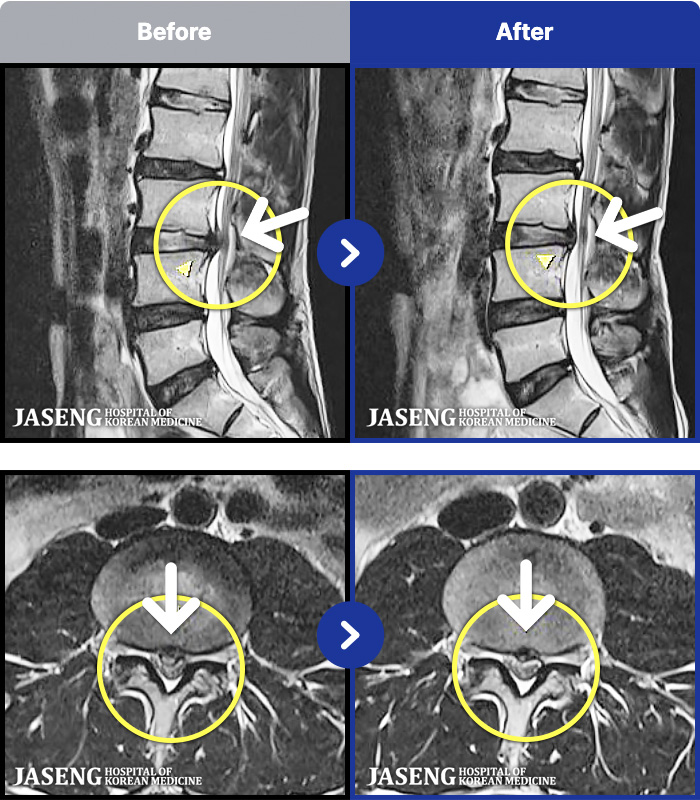

MRI ġ

MRI ũ ʸ Ȯϼ.